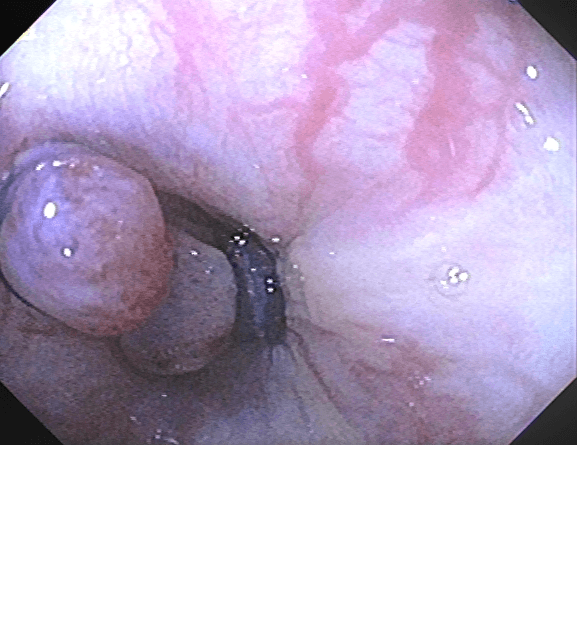

La ligadura endoscópica de várices esofágicas es un procedimiento terapéutico utilizado para tratar las dilataciones varicosas en el esófago, una complicación común de la hipertensión portal, especialmente asociada con la cirrosis hepática.

Durante la ligadura endoscópica, se utiliza un endoscopio flexible para guiar el paso de una liga de látex alrededor de las várices esofágicas. Esta liga de látex se coloca en la base de las várices, lo que provoca su estrangulamiento y eventual necrosis (muerte tisular). Este proceso reduce el riesgo de ruptura y sangrado de las várices, proporcionando un tratamiento efectivo para prevenir complicaciones graves como la hemorragia digestiva.